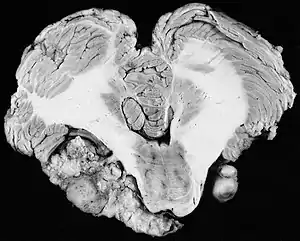

![]() | |

| Bilateral schwannomas in a patient with neurofibromatosis 2 | |

For the most part, unilateral sporadic vestibular schwannomas are readily treated successfully by modern medical techniques. Having bilateral VSs is a more troublesome condition. Bilateralism is considered to be the hallmark and main diagnostic criterion of Neurofibromatosis Type II (NF2), a genetic disorder that is heritable, progressive, difficult to manage, and has a 1 in 2 chance of being passed on to each offspring. NF2 patients tend to have a more severe mutation, although there are mild mosaic cases in which only some cells carry the mutation. Genetic testing confirming mutation of the NF2 gene is recommended. About 50% of people with NF2 have a de novo mutation, and about 50% of these new mutations will be mild mosaic cases which are less likely to be passed on. NF2 patients may develop other cranial and spine tumors. NF2 develops during the teens or early adulthood, whereas sporadic VSs are diagnosed mostly in patients between the ages of 40–60 years. Both varieties of VS (sporadic and NF2) are very rare, accounting for only about 8% of all primary brain tumors. The incidence of NF2 is approximately 1 per 60,000 people.[6][7][8]